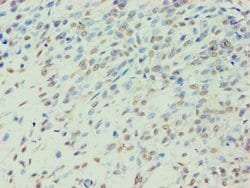

BCKDK Polyclonal Antibody for Western Blot, IHC (P), ELISA

| ELISA, Immunohistochemistry (Paraffin), Western Blot | |